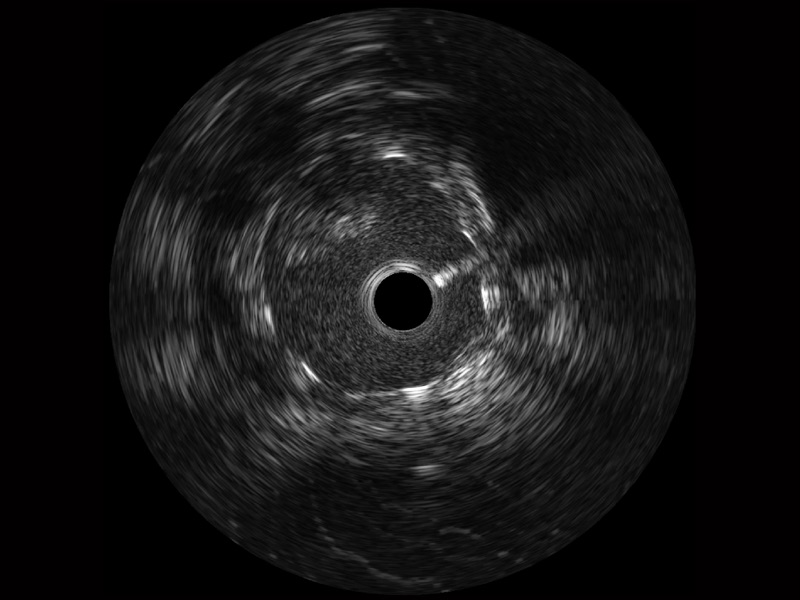

传统IVUS图像

对比传统IVUS导管成像,银河优越会宽频IVUS图像的近场支架梁显影更细腻,远场中膜外血管仍清晰可辨,兼顾远中近,兼顾分辨力与穿透深度